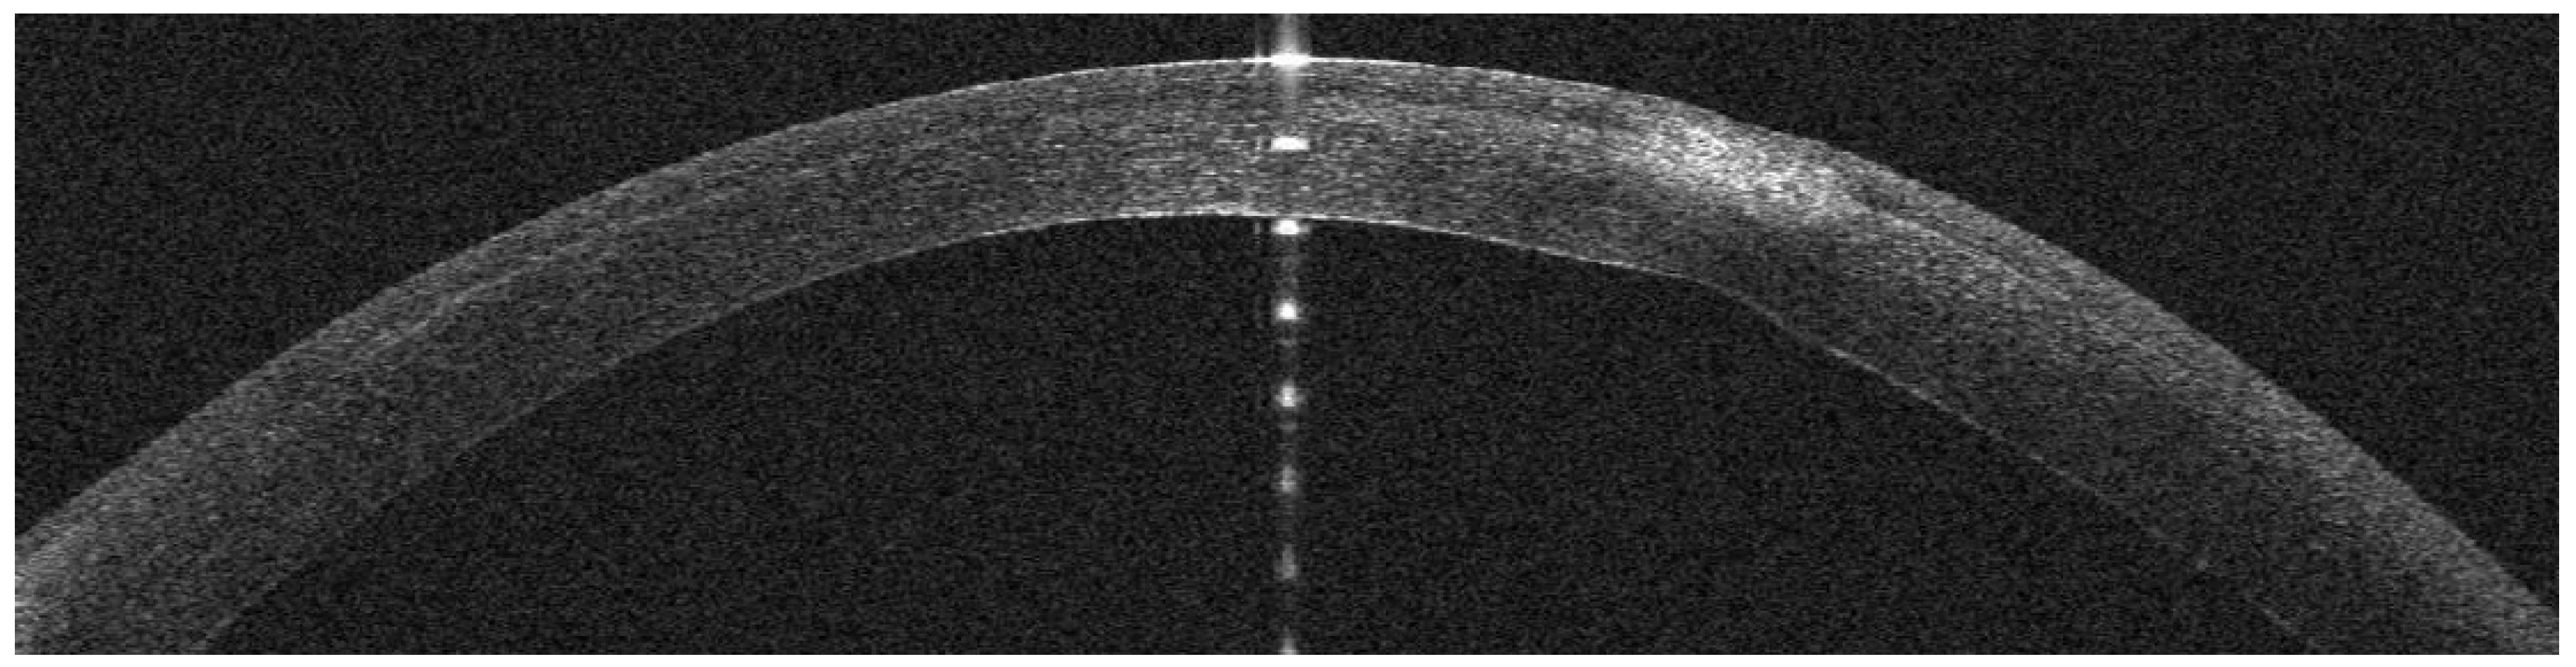

Infectious Keratitis Post-KLEx

AS-OCT Features